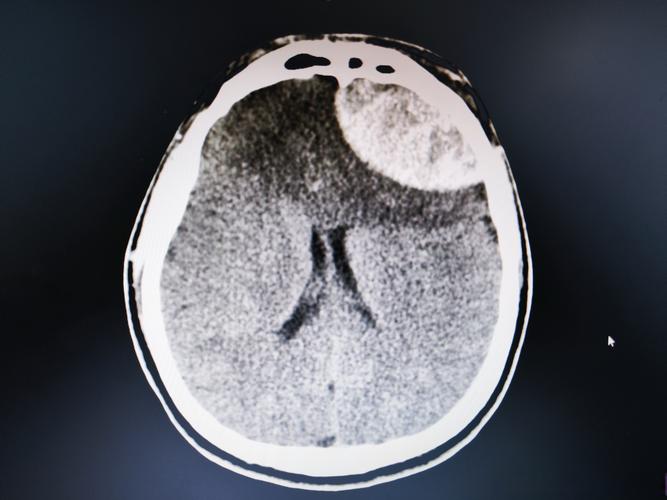

(图片来源网络,侵删)- 在脑梗发生的最初几个小时内(比如6小时内),常规的CT和普通MRI可能完全看不出任何异常。

- 但此时,细胞已经开始水肿,水分子弥散已经受限。DWI序列可以非常敏感地显示出病灶,比其他所有检查都早,这对于医生判断是否需要紧急进行溶栓或取栓治疗至关重要。